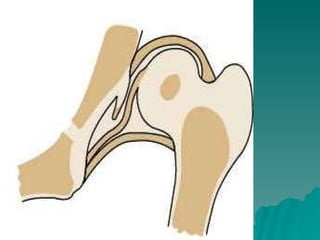

Developmental dysplasia of the hip is a condition where the hip joint is unstable or partially dislocated. It affects 1-50 out of every 1000 live births, with 60% being detected by 1 week of age and 90% by 8 weeks. The document discusses the anatomy, aetiology, pathology, clinical features, imaging, and different treatment approaches depending on if the patient is under 6 months, 6 months to 6 years, or above 6 years of age.